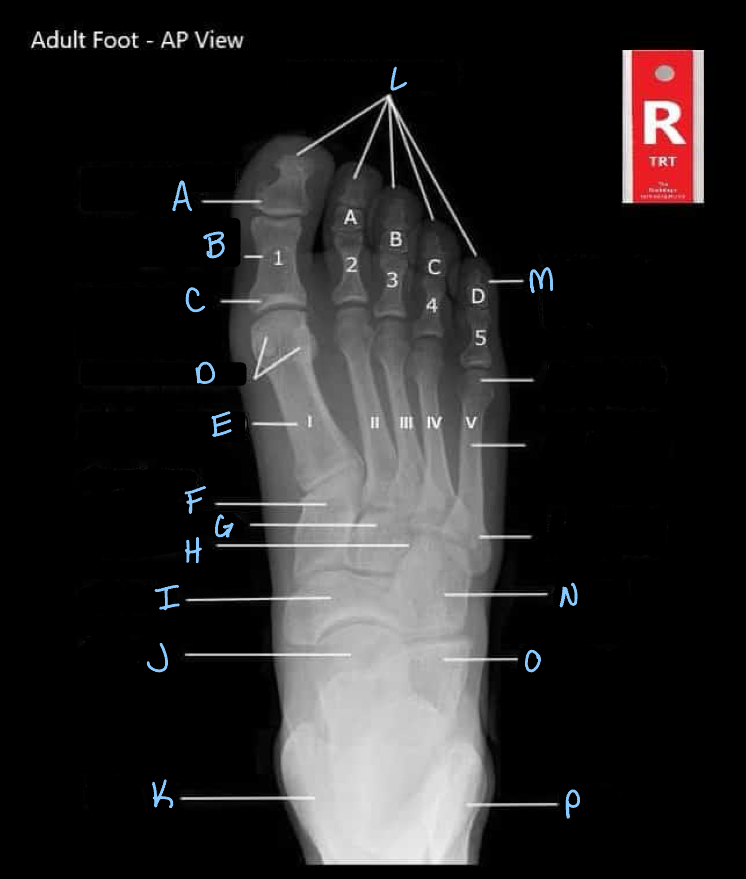

15

What is A?

interphalangeal joint

16

What is B?

proximal phalanges

17

What is C?

metatarsophalangeal joints

18

What is D?

sesamoid bones

19

What is E?

20

What is F?

medial cuneiform

21

What is G?

intermediate cuneiform

22

What is H?

lateral cuneiform

23

What is I?

24

What is J?

25

What is K?

tibia

26

What is L?

distal phalanges

27

What is M?

intermediate phalanges

28

What is N?

cuboid

29

What is O?

calcaneum

30

What is P?

fibula